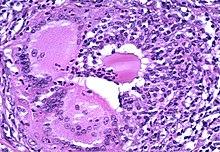

Microscopic image showing inflammation of the thyroid tissue

Thyroiditis is a group of disorders that all cause thyroidal inflammation. Forms of the disease are Hashimoto's thyroiditis, the most common cause of hypothyroidism in the US, postpartum thyroiditis, subacute thyroiditis, silent thyroiditis, drug-induced thyroiditis, radiation-induced thyroiditis, acute thyroiditis, and Riedel's thyroiditis.[1]